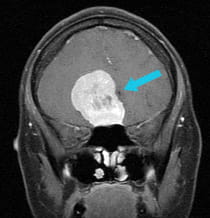

post-surgical scan of successful removal of large tumor via endoscopic endonasal approach surgery

Post-surgical scan show the successful removal of the large tumor via EEA surgery.

The Solution

Using EEA, UPMC surgeons removed the tumor without lifting the brain. Because of the height of the tumor, the surgeons removed the tumor in two steps, allowing the top of the tumor to fall down to them once the lower portion was removed, rather than chasing it up into the delicate reaches of the brain.

The Result

The entire meningioma was successfully removed using this surgical approach, and the patient's vision was restored.